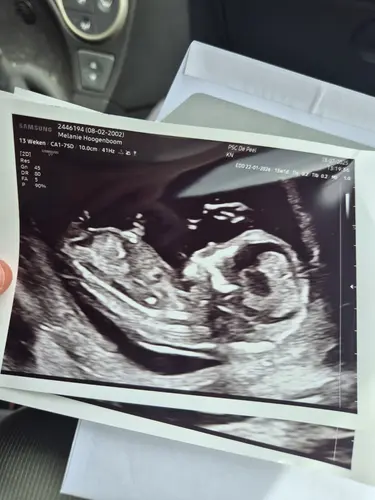

Hoi Dames,

Ik ben ook al een tijdje aan het kijken naar de Nub Theorie methode en o m g … ik kom er gewoon niet uit 🫣 hier zijn jullie een echo foto van mijn tweelingen 🤭 enig idee wat jullie met Nub kunnen zien? Ben benieuwd 🤗 veel succes voor alle aanstaande moeders/ouders 🤍💛